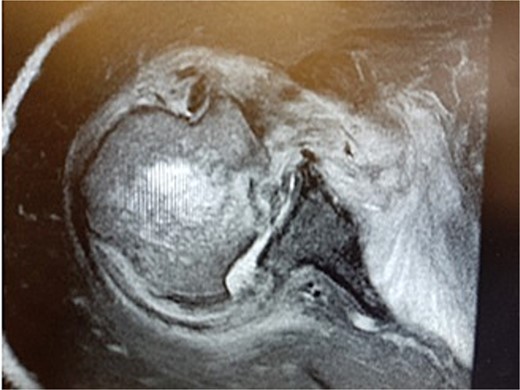

During the outpatient follow-up visit at the Orthopedic Clinic, ~10 weeks after the accident, a physical examination of the patient was conducted, which included shoulder X-ray imaging. The examination revealed severe pain in the right shoulder and a significant limitation in the mobility of the joint (results summarized in Table 1). The above enforced the decision of expanding the imaging diagnostics to look for fractures within the humeral head; hence, computed tomography (CT) and magnetic resonance imaging (MRI) examinations of the right shoulder were carried out. Additional imaging studies revealed a depression fracture of the humeral head covering 2/3 of the articular surface with posterior subluxation of the right shoulder joint. The examination also revealed that the continuity of the tendons of the rotator cuff muscles has been preserved.

MRI images can be found in Figs 3 and 4, and CT images in Fig. 5.

The lack of sufficient effects of the applied conservative treatment resulted in the patient being qualified for the orthopedic surgery.